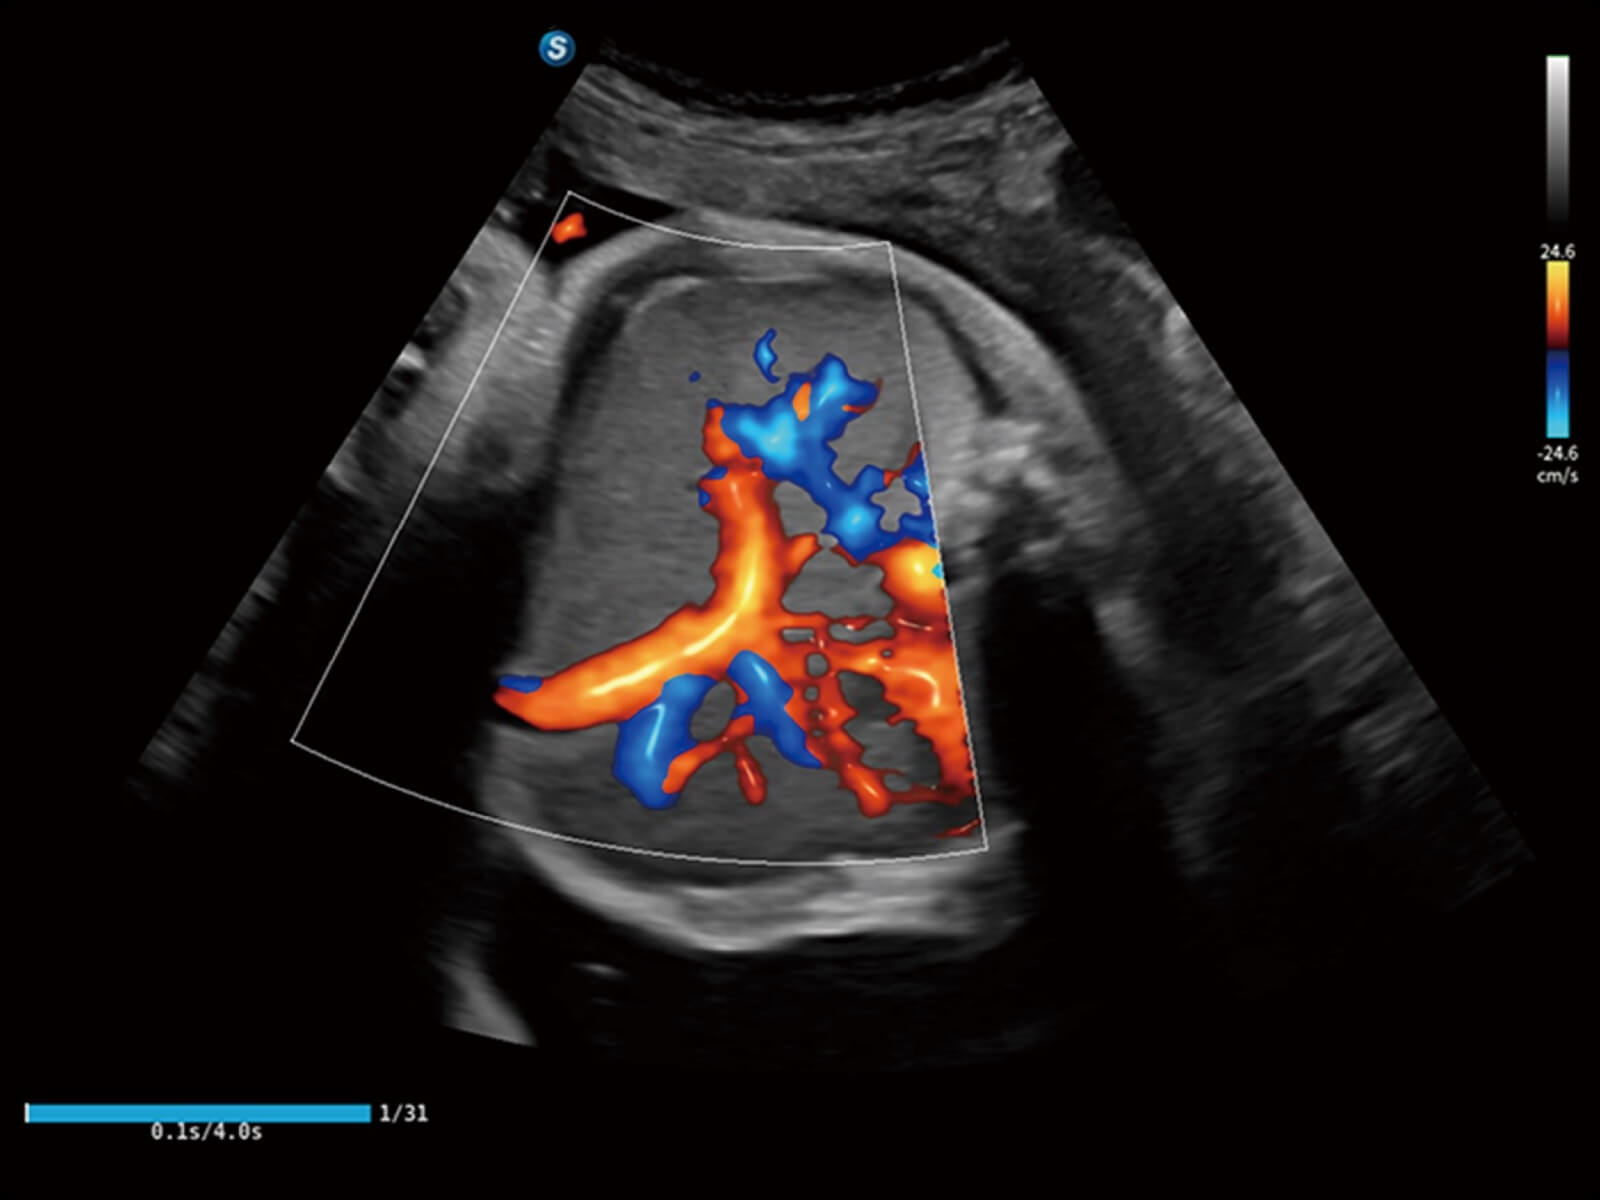

Bright Flow立体血流成像

通过光照模型,使二维血流显示出立体的效果,增加血流的敏感性、成束性,减少外溢。可以和其他不同的血流技术联合使用,轻松应对微小血管,增强血流的立体效果,提升视觉敏感性。